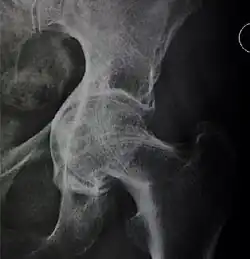

X-ray of the hips of a 40-year-old female, with dysplasia of her right hip.